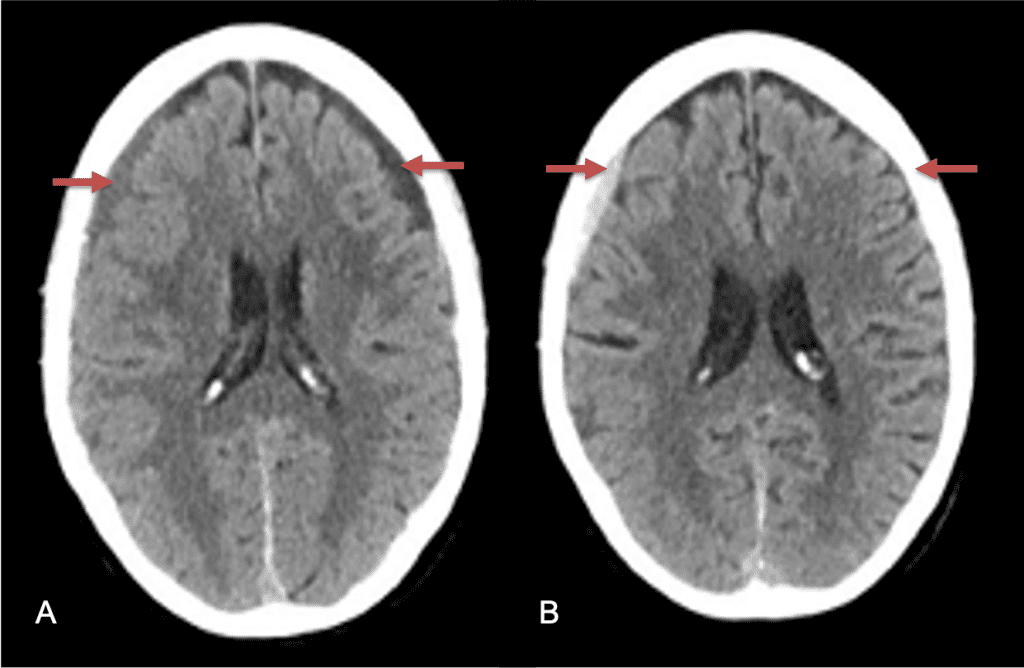

CT follow-up at 1 week demonstrates early resorption. 2 weeks post MMA embolization, resolution of the left subdural collection with new small thin acute hemorrhage in an otherwise stable right subdural collection is observed (Figure 3. A and B).

Figure 3. A) 1 week post MMA embolization demonstrating decreasing thickness bilaterally B) 2 weeks post MMA demonstrates resolution on left, with small new acute component on right with overall decreased thickness.

Clinically, the patient improved over the few weeks with the occasional transient twinge of a headache, but resolution of dizziness. Follow-up CT at 10 weeks demonstrated complete resolution of the bilateral subdural hematomas with our patient completely asymptomatic and back to all of her activities of daily living. Considering her history of thrombocytopenia and CLL, we will continue to monitor her into the future and are excited about her progress and recovery. (Figure 4. A and B)

Figure 4. A and B) – 10 weeks following embolization demonstrates complete resolution of bilateral collections both acute and chronic.